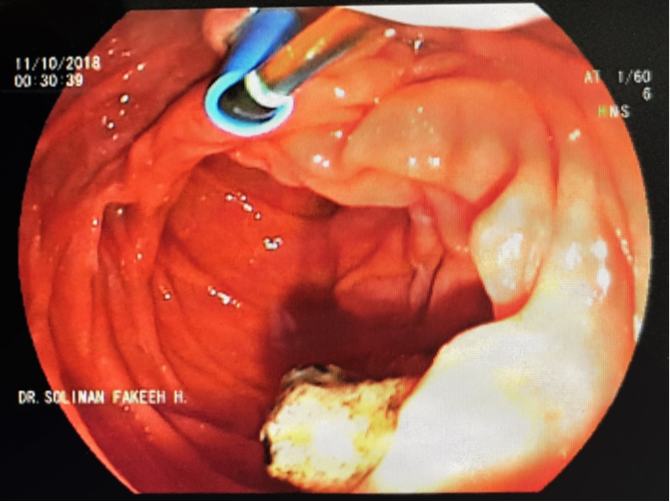

A 59-year-old female with multiple co-morbidities including ischemic heart disease with coronary artery bypass grafting in 2016, diabetes mellitus, hypertension. She presented with fever, abdominal pain related to chronic calcular cholecystitis and poor oral intake referred to examined by general surgery and they recommend to start antibiotics course and to be re-assessed again in a week time. After four days, patient came to the emergency department with severe septic shock, blood pressure as low as 80/40 mmHg refractory to fluids resuscitation. Radiological investigations revealed severe ascending cholangitis, impacted biliary stone at level of ampulla of vater, complicated by liver abscess and anuric acute kidney injury with refractory hyperkalemia and metabolic acidosis requiring urgent renal replacement therapy. Patient was transferred immediately to intensive care unit. In view of dilated biliary radicles with signs of biliary stone impaction, urgent endoscopic retrograde cholangiopancreatography (ERCP) was performed, with stent insertion and pulling out of a large pigmented stone and drainage of biliary muddy fluid (Figure 1). Immediate continuous renal replacement therapy in the form of continuous venovenous hemodiafiltration (CVVHDF) was initiated to correct the metabolic and electrolytes disturbances in order to save the patient life.

A) Pigmented biliary stone obstructing Ampula of Vater.

B) Stent of the common bile duct for drainage.

Figure 1 ERCP and dislodge of impacted biliary stone at ampulla of Vater.